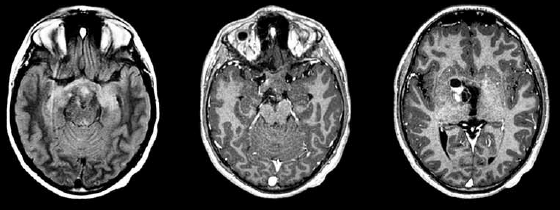

Paciente de 2 anos apresenta nistagmo e perda visual há 3 meses. Realizou o exame de imagem a seguir.

Qual é o provável diagnóstico?

Paciente de 2 anos apresenta nistagmo e perda visual há 3 meses. Realizou o exame de imagem a seguir.

Qual é o provável diagnóstico?